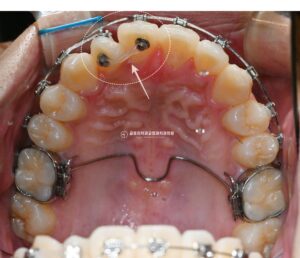

안녕하세요, 중랑구 교정치과 김정은원장입니다. 24.10.18 정면에서 보았을 때 턱의 위치가 옆으로 기울어져 보이거나 위아래 앞니의 중심선이 맞지 않는 느낌이 든다면 신경이 쓰일 수 있습니다. 이러한 안모 비대칭은 단순한 배열의 문제가…